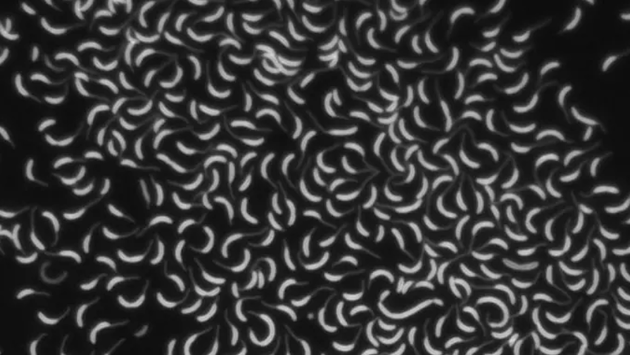

Американские ученые исследовали взаимодействие белков и клеточной оболочки бактерии Caulobacter crescentus. В ней белок OpgH создает глюкозосодержащие молекулы OPGs, способствующие антибиотикорезистентности. Оказалось, что при уменьшении количества OpgH выработка молекул останавливается, из-за чего клеточная оболочка бактерии начинает деформироваться. Это приводит к гибели микроорганизма. В будущем полная информация о выработке глюкозосодержащих молекул и работе ферментов позволит создать новые антибиотики против сальмонеллы, кишечной палочки и других инфекций. Исследование опубликовано в журнале mBio.Антибиотикорезистентность — одна из самых серьезных угроз для здоровья населения по всему миру. Бактерии продолжают эволюционировать и становятся невосприимчивыми к лекарствам, которые ранее использовались для их уничтожения. Это приводит к увеличению риска смерти пациентов, возрастанию затрат на здравоохранение и неизлечимости некоторых инфекций. Сегодня ученые работают над тем, чтобы победить антибиотикорезистентность и найти универсальный способ воздействия на бактерии.Американские исследователи решили выяснить, как можно разрушить клеточную оболочку, защищающую пресноводную бактерию Caulobacter crescentus. Они сосредоточились на ферменте OpgH. Он создает глюкозосодержащие молекулы (OPGs), которые заполняют промежутки между защитными оболочками клеток. Хотя сами Caulobacter crescentus не вызывают заболеваний, ее OPGs играют определенную роль в развитии устойчивости к антибиотикам.Исследователи наблюдали за тем, как OpgH влияет на сигнальный путь CenKR, выявляющий и устраняющий изъяны в клеточной оболочке. Ученые экспериментировали с количеством белков, уменьшая и увеличивая их концентрацию, тем самым гиперактивируя путь CenKR. После этого исследователи поместили бактерий на гелевую подложку, которая препятствовала их перемещению, и с помощью микроскопа отследили изменения в их форме и активности. Оказалось, что при снижении уровня белка OpgH остановилась выработка молекул OPGs, из-за чего клетки бактерии стали деформироваться. Тоже самое происходило при гиперактивации сигнального пути CenKR. Деформация коснулась и клеточной оболочки — она потеряла свою структуру, в результате чего бактерия погибла.Теперь ученые планируют исследовать все ферменты, которые создают глюкозосодержащие молекулы, и составить полную картину того, как они поддерживают работу клеточной оболочки. В будущем результаты позволят разработать новые лекарства, нацеленные на эти ферменты и способствующие гибели бактерий — например, бруцеллы, псевдомонады, сальмонеллы и кишечной палочки.